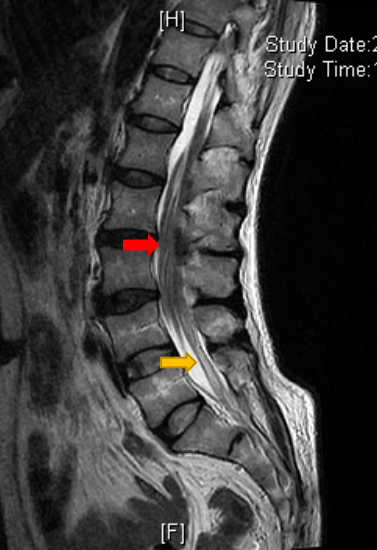

今年1月份,翟先生发现自己小便困难,甚至尿不出来,到当地医院检查后未得到确切病因诊断,经当地医师推荐,翟先生身带7个月的尿管从内蒙古来到北京清华长庚医院求助。神经外科孙振兴医师接诊后,联合泌尿外科刘宇保医师完善相关检查,排除泌尿系统问题后,通过腰椎核磁共振找到了病因——系脂肪瘤型脊髓拴系综合征导致的中枢性排尿障碍。

红色箭头处可见脊髓低位,马尾神经拥挤,黄色箭头处可见终丝增粗,可疑脂肪瘤变

“脊髓拴系综合征是脊髓被固定于特定异常状态所引起的相关症状的一个总称。各种原因(如先天畸形)引起脊髓被牵拉,生理性移动范围缩小,导致脊髓末端低位,发生脊髓圆锥的病理生理异常,进而引起脊髓和神经的慢性或急性的损伤,表现为大小便和下肢的感觉运动功能障碍。”孙振兴医师说,这个病大多是先天性的,翟先生虽然一直没发现这个病,但贵在发病时能尽早地确诊并得到有效的治疗,避免了脊髓和神经无法挽回性的损害。